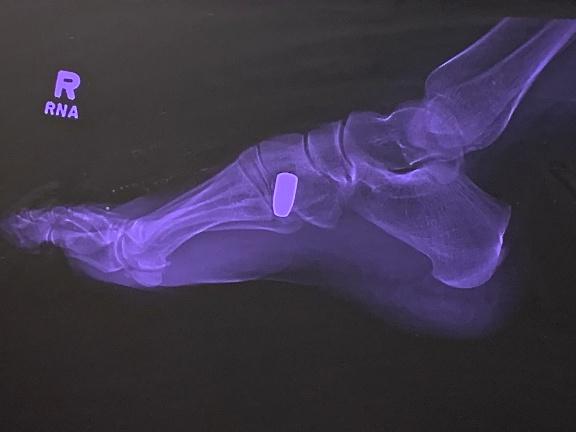

As I sat there holding pressure on the wound and waiting for the ambulance, I couldn’t help thinking this wasn’t the kind of challenge I expected in real estate. At the hospital, the X-rays showed a 9 millimeter bullet lodged in my foot. I had been shot and didn’t even know it.

With all that being said, I never imagined getting shot would be part of the job. Yet there I was with a bullet in my foot. The police believed someone fired a gun into the air somewhere within a two-mile radius, and I was simply in the wrong place when it came down. Or was it the right place?